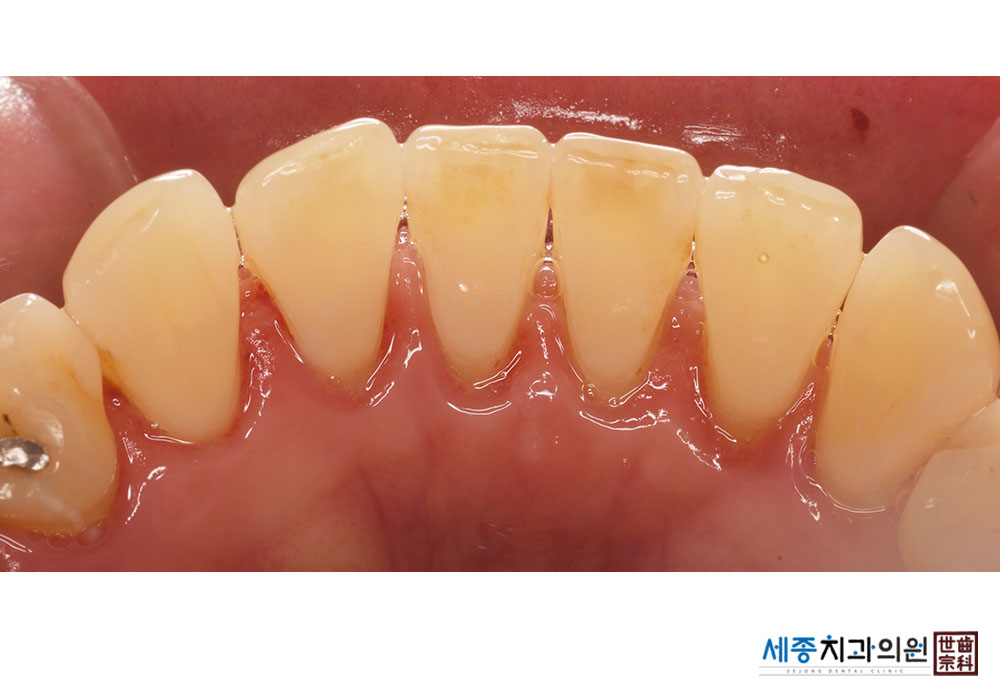

[스케일링] 치주질환 예방 스케일링

치료전 : 2023-01-20

치료후 : 2023-01-20

가글마취&저주파 스켈러를 사용한 스케일링